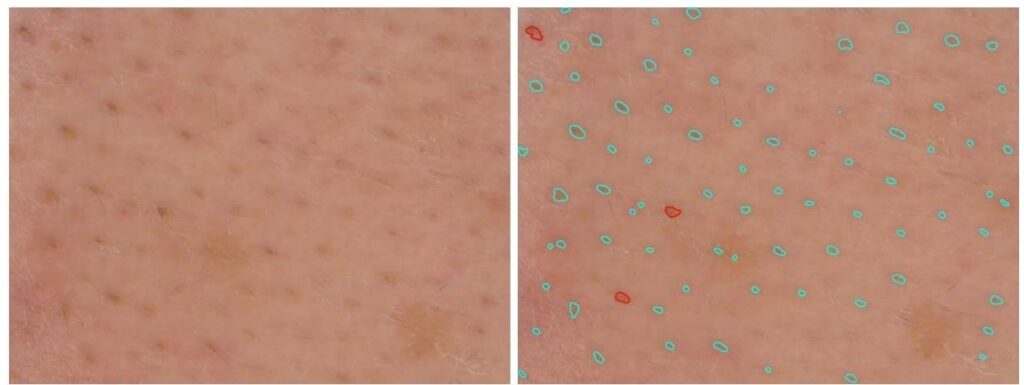

Analyse des pores

La production excessive de sébum peut avoir une incidence sur la taille des pores. Ces derniers peuvent se dilater. Grâce à ses mesures dimensionnelles fiables et son calibrage métrique, le C-Cube peut détecter le nombre de pores et les mesurer, en 2D et en 3D.

En 2D, cela consiste en l’analyse des couleurs, suivie par l’identification des formes pour éliminer d’autres objets et conserver uniquement les pores. Les résultats consistent en des images traitées en noir et blanc. Vous obtenez aussi une feuille de calcul avec la zone médiane, le diamètre médian et la densité des pores de chaque image.

L’analyse 3D fournit une dimension supplémentaire de la profondeur des pores. L’approche 3D améliore la sensibilité de la détection des pores. Elle permet alors d’évaluer la profondeur des pores et leur éventuel remplissage.

Image source Image traitée